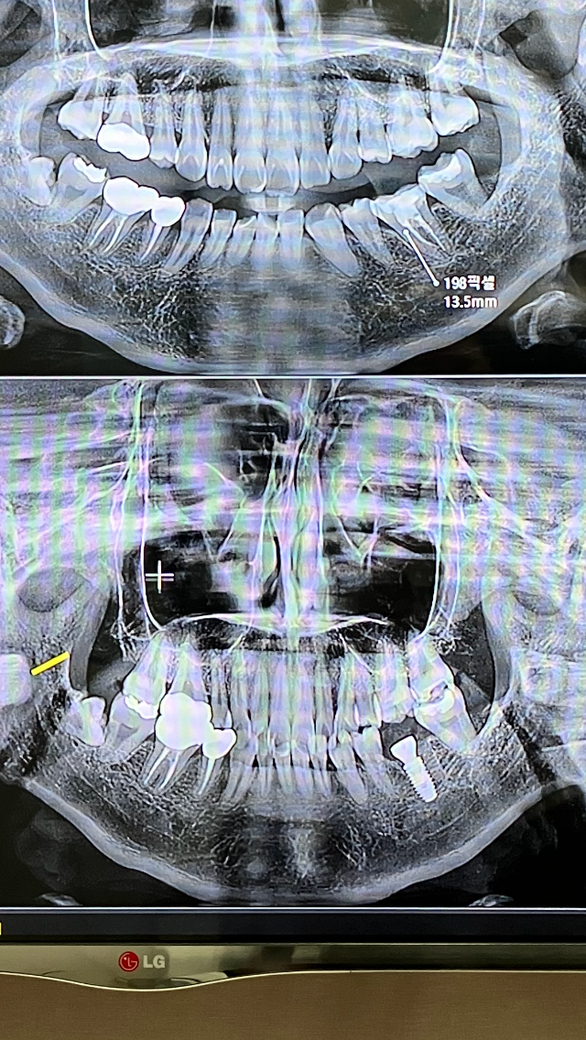

임플란트하고 옆치아가 욱신 거리면서 아프기도하나요?

앞치아가 욱신거리면서 약간 땡기는 느낌? 이 나는데 괜찮겠죠?ㅠㅠ

사진상으로는 잘 식립되어 있습니다. 통증이 지속된다면 치과에서 검사 받아보시는 게 좋습니다.

사진상으로는 임플란트 수술은 특별히 무리 없이 잘 진행되었고 신경관과의 거리도 괜찮아 보입니다. 임플란트를 심은 부위의 앞 치아가 불편감이 있다면 이는 임플란트 수술과는 별개일 수도 있습니다. 해당 치아에 대한 별도의 검진을 받아보시기 바랍니다.

아니면 주변 잇몸 통증을 그렇게 느끼시는 것일 수도 있습니다. 임플란트 수술 후 일시적 불편감이 며칠 정도 있을 수 있습니다.